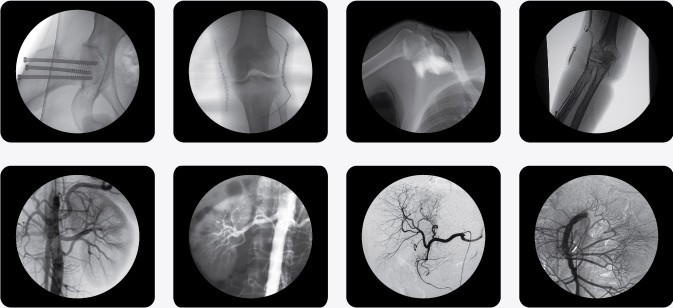

一、C型臂X光機(jī)PLX7000B的用途

廣泛應(yīng)用于 介入科、骨科、外科、矯形外科、泌尿外科、脊柱外科、腹部外科、疼痛科、心臟科、消化科、婦科及手術(shù)室等。

三、C型臂X光機(jī)PLX7000B數(shù)字高清影像,支持您做出精確診斷

·全數(shù)字化百萬像素影像采集系統(tǒng),優(yōu)化設(shè)計(jì)和配置,為您提供高分辨率、高灰階圖像,支持您做出精確診斷。